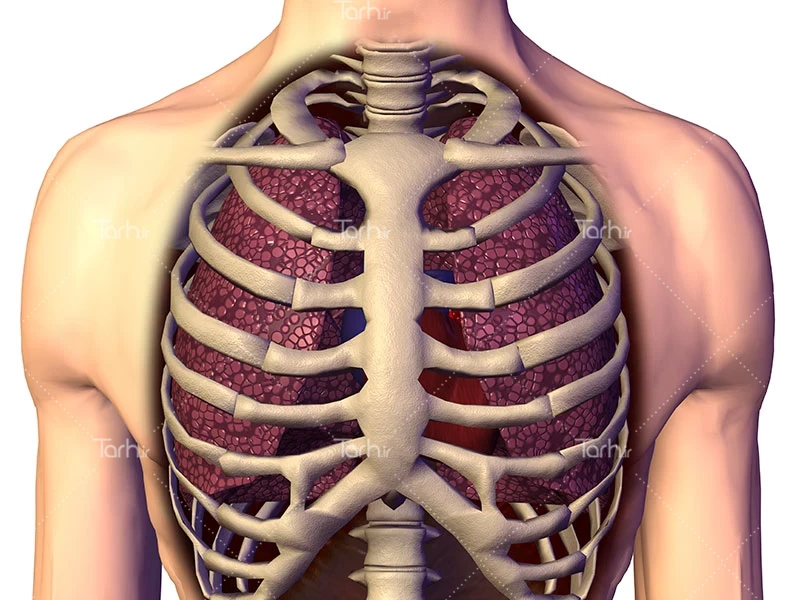

عکس باکیفیت آناتومی قفسه سینه کد فایل 5460546

دانلود تصویر باکیفیت آناتومی قفسه سینه با فرمت jpg برای طراحی شما می توانید از این تصویر استفاده کنید همچنین برای چاپ کاغذ دیواری و پوستر در ابعاد بزرگ میتوان استفاده کرد.

دانلود تصویر باکیفیت آناتومی قفسه سینه,تصویر باکیفیت آناتومی قفسه سینه,عکس استوک کیفیت بالای آناتومی سه بعدی قفسه سینه,تصویر استوک باکیفیت آناتومی قفسه سینه انسان,بدن انسان,بدن,انسان,آدم,آناتومی,آناتومی سه بعدی,آناتومی قفسه سینه,آناتومی سه بعدی قفسه سینه,اعضای داخلی بدن انسان,اعضای داخلی بدن,تصویر سه بعدی استخوان های قفسه سینه انسان,عکس باکیفیت اعضای داخلی بدن انسان,قفسه سینه,استخوان های قفسه سینه,قفسه سینه,شش,ریه,قلب